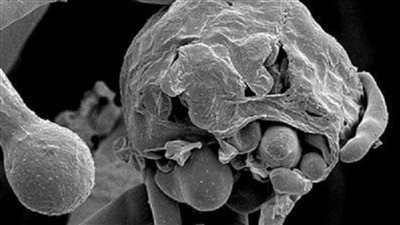

استشاري مناعة توضح خطورة الفطر الأبيض على الرئة وعلاقته بكورونا

"هانى الناظر" يوضح حقيقة مرض الفطر الاسود "اعراضه وخطورته وعلاقته بفيروس كورونا"